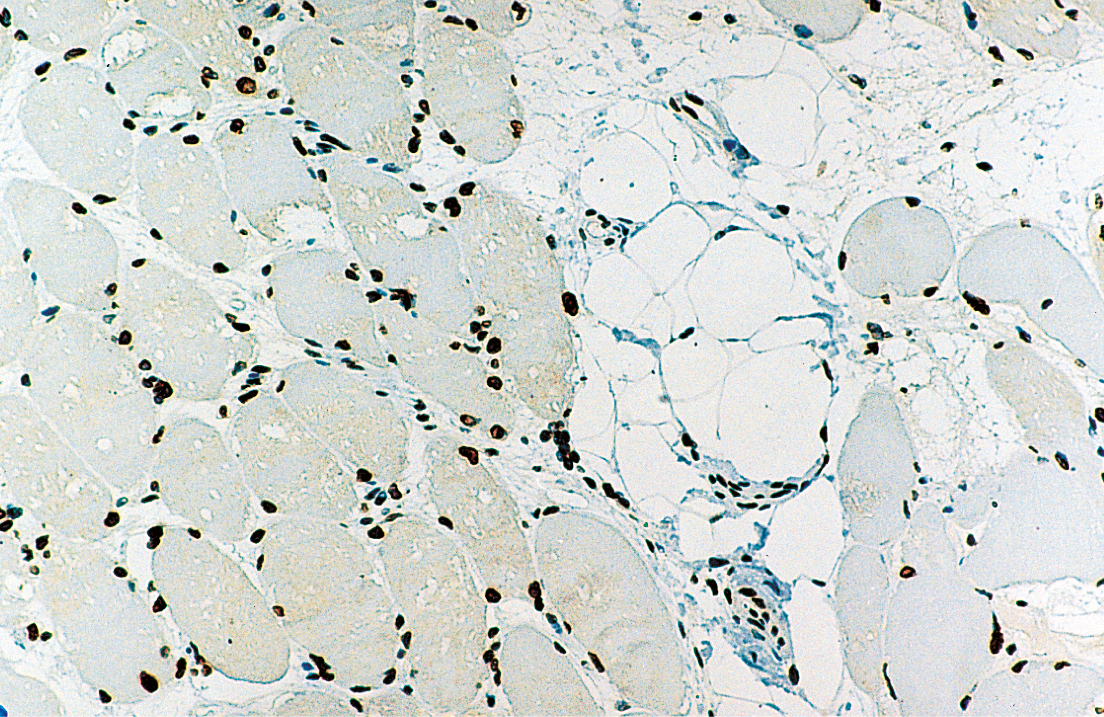

Human skeletal muscle: immunohistochemical staining for Emerin. Note perinuclear staining of all cell nuclei. Emerin: clone 4G5

Die Kontrakturen treten an den Ellenbogen, Achillessehnen und der postzervikalen Muskulatur auf, mit einer humero-peroneal betonten Muskelschwäche in der Frühphase der Erkrankung. Das STA-Gen, dessen Lokus sich auf Xq28 befindet, kodiert ein serinreiches Protein von 34 kD, Emerin, das im Gewebe allgegenwärtig ist und dessen höchste Konzentrationen in der Skelett- und Herzmuskulatur nachweisbar sind.

Emerin befindet sich in der Kernmembran normaler Muskelzellen, und sein Mangel spielt eine wesentliche Rolle bei der Pathologie der EDMD. NCL-EMERIN ist hilfreich zum Nachweis des normalen Genprodukts von STA.